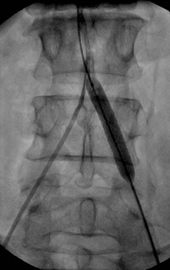

Απεικονιστικές εξετάσεις για τη διερεύνηση της διαλείπουσας χωλότητας αποτελούν το έγχρωμο duplex (triplex), η αξονική αγγειογραφία, η μαγνητική αγγειογραφία και η ψηφιακή αφαιρετική αγγειογραφία.

Σε περιπτώσεις διαλείπουσας χωλότητας μη περιοριστικού τύπου συνήθως η θεραπεία είναι συντηρητική. Αυτή περιλαμβάνει φαρμακευτική αγωγή, ρύθμιση παραγόντων κινδύνου, διακοπή του καπνίσματος και επιτηρούμενο πρόγραμμα άσκησης. Σε περιπτώσεις κρίσιμης ισχαιμίας ή σοβαρής διαλείπουσας χωλότητας η αντιμετώπιση είναι συνήθως επεμβατική, είτε με αγγειοπλαστική με ή χωρίς stent, ή χειρουργική.